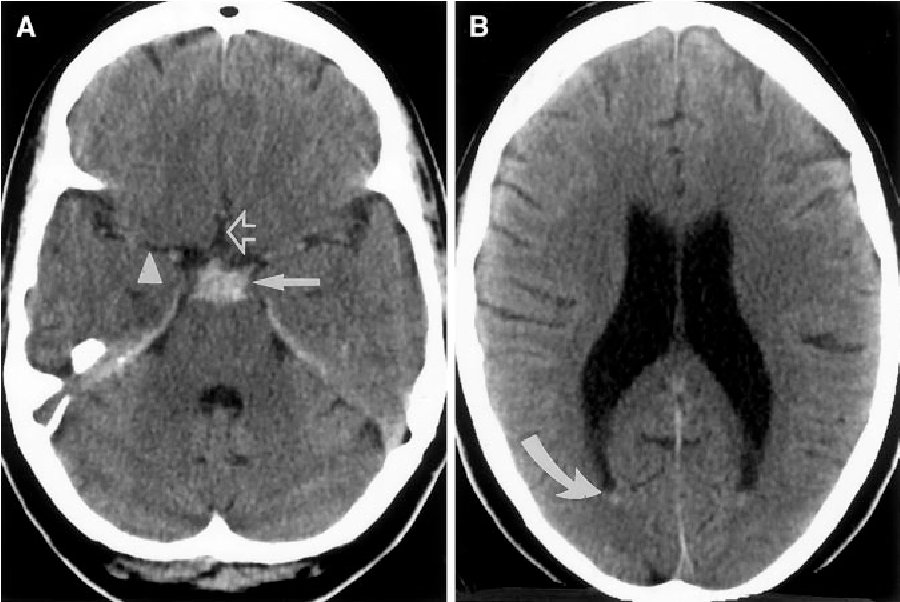

لا الاشعة فيها نزيف..bilateral subacute subdural hge

ودي واحدة من الحاجات اللي سهل جدا تmiss خصوصا لو مستني تلاقي شكل النزيف الابيض الكلاسيكي

ونزيف ازاي والاشعة free؟؟

الsubdural hge بيمر ب3 مراحل (acute-subacute-chronic) كل واحدة بتاخد اسبوع تقريبا ، الدم علي حسب تحلله جوا الجمجمة بيكونله كثافة مختلفة بالتالي اشكاله بتختلف

الsubacute بيكون isodense في فيلم الاشعة ، يعني لونه قريب جدا من لون نسيج المخ الطبيعي فمش هتعرف تفرق بينهم

الموضوع دة لو حصل unilateral يبقي اتحلت، لانك كدة كدة هتشوف الmidline shift..

لكن لو bilateral ، ساعتها مش هتشوف اي حاجة....ساعات بيبقي حظك حلو وتشوف خط فاصل بين النزيف وبين المخ(مع انهم نفس اللون) لكن الاكيد هتشوفه ان الgreywhite interface بقي limited اوي medially

بس قصة انها limited ولا لا ، دي حاجة subjective جدا ومحتاجة واحد متمرس..فصعب نعول عليها..

الفيصل فيها هو الرنين ، ساعتها هيبين الفرق بين نسيج المخ الطبيعي وبين النزيف،طبعا حلها تدخل جراحي

الخلاصة: ان الsubacute subdural لونه رمادي زي المخ بالظبط